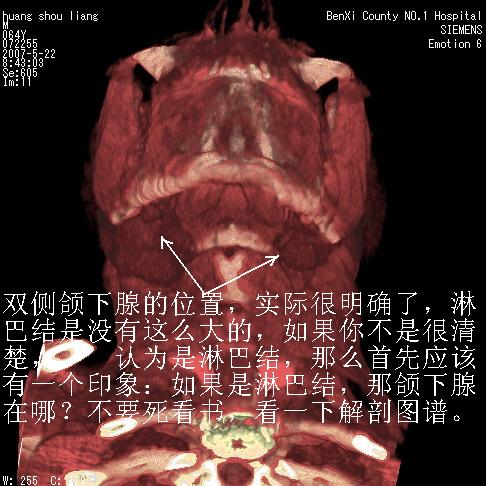

对不起大家,可能是片子发太多有点乱,正常腮腺在下颌角的外侧,颌下腺在下颌体的中部内侧,本例在下颌角内侧偏下,和腺体一点关系都没有,从vrt和mpr上可以很明显看出来,再者肿块是好多粘连在一块的,大家在仔细看看,左侧可能也是吧,我还是考虑为肿大的淋巴结融合在一块,但性质??????

大家好,病理结果出来了,如大家所说,颌下腺混合瘤。

唉,解剖没学好吧,我诊断错了,不过还是有些不理解回去我在多看看书,谢谢大家的参与,以后我还会奉献好的病例。

画个图共同讨论一下解剖关系。